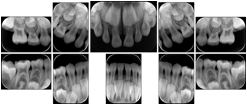

2. A patient requests cosmetic surgery to enhance their facial appearance. The case requires consultation between an orthodontist in New York and an oral surgeon in California. The cephalometric series of 2D projections constructed from the volumetric CT data that is used for the discussion is arranged by a Structured Display for transfer between the two practitioners.

Cephalometric Series Structured Display

Figure OO-2. Cephalometric Series Structured Display